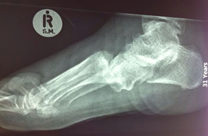

Imaging

- Important to rule out fractures.

- If possible, request weight bearing X-rays when lisfranc injuries are suspected.